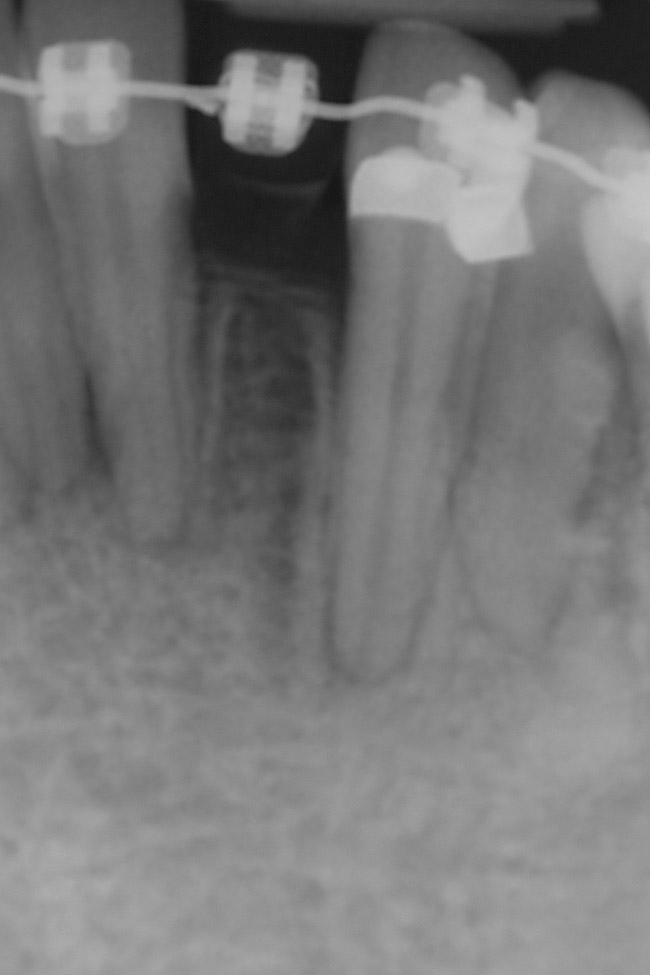

Figure 10  Radiograph of orthodontic distraction osteogenesis.

Figure 10

Figure 11  Radiograph showing developed implant site of tooth No. 23.

Figure 11